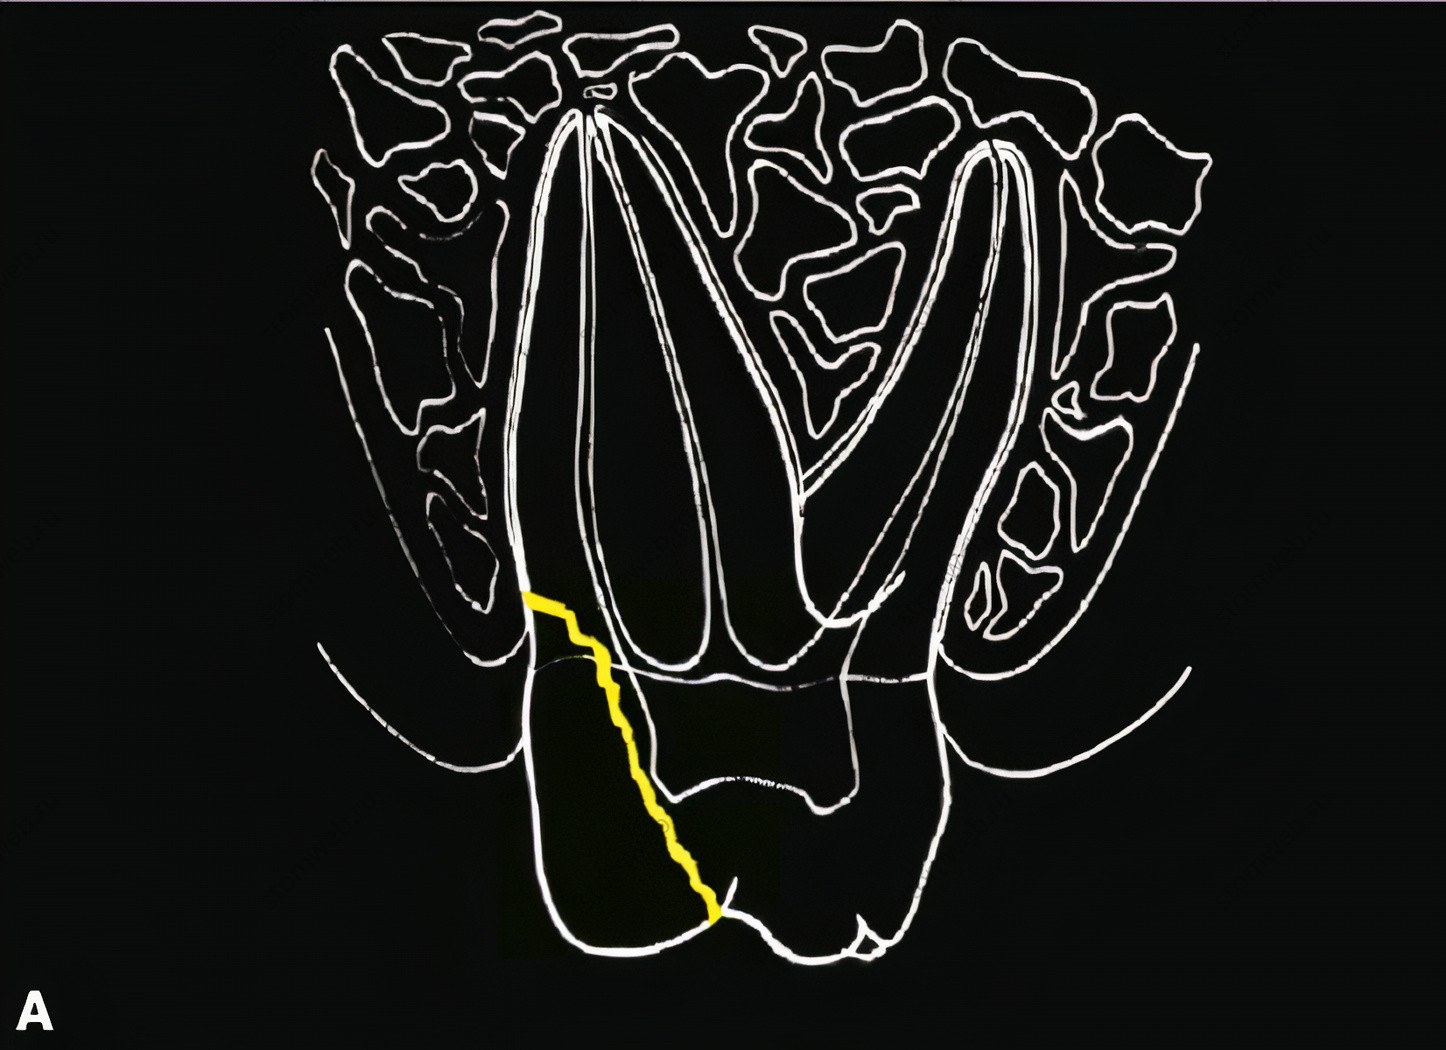

Зубы трескались столько же, сколько и существует человечество; в черепе, которому около 6500 лет, не просто найдены зубы с переломом, трещина была заполнена пчелиным воском, видимо, с целью убрать симптоматику. Недавно Gibbs создал термин «боль при отломе бугра» для ситуаций, когда появлялись симптомы, а при осмотре были найдены трещины под буграми, часто приводящие к полному отлому бугра (Рис. 4). Термин «синдром треснутого зуба» был предложен Cameron и сразу же был принят для симптоматичных зубов с наличием трещин в их коронках. Термин хоть и принят, слово «синдром» все еще вызывает вопросы. Синдром предполагает некоторую комбинацию признаков и симптомов, которые означают определённое заболевание или расстройство. В зубах с синдромом треснутого зуба предполагаемый диагноз основывается на наличие таких симптомов как боль при накусывании и реакцию на холодное. Пусть синдром треснутого зуба и не является синдромом, он стал настолько часто выявляться за последние 50 лет, что его пришлось принять для обозначения симптоматичных зубов с переломами коронок.

Рисунок 4. Переломы бугров. А. Графическая иллюстрация, показывающая обычное направление трещины бугра. Линия трещины обычно огибает пульпарную камеру, не затрагивая ее. В. Клинический пример перелома бугра; если пульпа не затронута, эндодонтического лечения можно избежать.